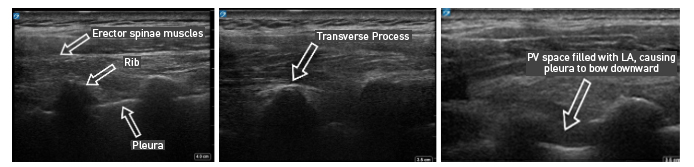

With PVB, deposit local anesthetic between the pleural and costotransverse ligament under ultrasound guidance using either an in-plane or out-of-plane needle approach. For the out-of-plane technique, hold the transducer (linear or curvilinear, depending on the patient’s body habitus) in the sagittal plane, allowing for a linear needle trajectory perpendicular to the skin (Figure 3). The pleura is visible in that plane between the ribs laterally and the transverse processes medially. In the transition from rib to transverse process, the bone image appears larger and squarer as the transducer is moved more medially (Figure 4). Hydrodissect with sterile saline to estimate the needle tip location when using an out-of-plane technique, with the downward/anterior bowing of pleura, or loss of reflection of saline upward/posterior, indicating injection into the paravertebral space. This is the preferred regional anesthetic technique at our institution and has provided effective surgical anesthesia for a variety of oncologic breast and thoracic procedures.

Figure 4: Ultrasound images of paravertebral block via out-of-plane technique

With the patient seated, apply standard ASA monitors, administer supplemental oxygen, and initiate intravenous fluid administration. Sedation generally includes midazolam (2 mg) and/or fentanyl (50–100 mcg). Following sterile prep, position the ultrasound probe in the sagittal plane adjacent to the planned vertebral level approximately 3 cm off of the midline of the spine (Figure 3). Scanning from medial to lateral, first identify the transverse process and rib, taking note of their transition by change in shape and depth (Figure 4). Both structures will be seen in cross-section with pleura located anterior to the cephalad and caudad bony structures. Targeted injections should occur after the transition from rib to transverse process (the transverse process is located more medially and appears more squared-off in appearance).

Taking note of the depth of the pleura, center the structure on the ultrasound screen and anesthetize the patient’s skin with lidocaine lateral and adjacent to the middle of the probe. The costotransverse ligament is located posterior to the pleura (occasionally difficult to visualize on ultrasound imaging) and injections in the space between the costotransverse ligament and pleura should provide effective PVB. Insert the block needle approximately 1–2 cm less before the pleura using the depth indicators on the nerve block needle. The local anesthetic for the block and a syringe of sterile saline are attached to the block needle via a three-way stopcock, initially open to saline and previously flushed with saline to remove all air. Give a small but firm push of the saline flush to provide an estimation of needle tip position. Advance the needle in small increments until the saline is no longer seen reflecting superficially from the pleura. Placing the needle tip in the paravertebral space will result in anterior pleural deflection in a bowing-like manner and can usually be visualized spreading superiorly and inferiorly in adjacent paravertebral spaces. Skip one or two levels between injection points, depending on the incision site (eg, SLNB in axilla), tumor location, or patient anatomy.